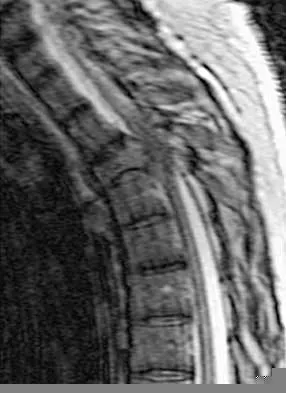

A 60-year-old woman with a history of breast cancer has progressive paraparesis. The MRI scan is shown in Figure 28. What form of management is most likely to restore or maintain ambulation?

Explanation